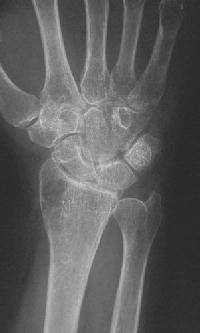

Clinical Example: Distraction plate fixation distal radius fracture

distal radius fracture

distraction plate